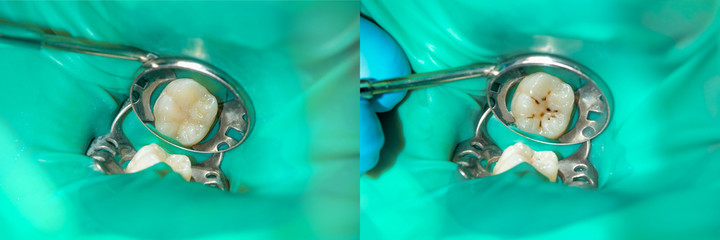

Read MoreDental Filling

At different stages of development, your child may have baby teeth, permanent te